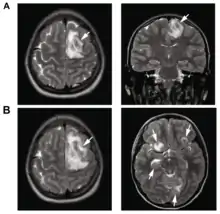

| T2-weighted MRI showing a necrotic brain absess as a result of GAE caused by an infection of Acanthamoeba, genotype T18 | |

B: T1-weighted MRI showing expansion of the brain lesions 4 days later